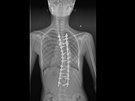

Snímek vychýlené páteře po aplikování unikátních rostoucích tyčí. Snímek skoliózy před léčbou. Martin Repko (uprostřed) je přední evropský odborník na operace zakřivení... Martin Repko (uprostřed) je přední evropský odborník na operace zakřivení... Martin Repko (uprostřed) je přední evropský odborník na operace zakřivení... Martin Repko (uprostřed) je přední evropský odborník na operace zakřivení...